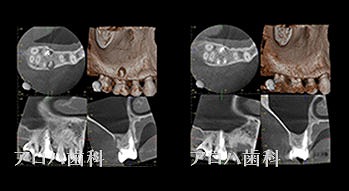

case3

再根管治療

1年予後

瘻孔の消失